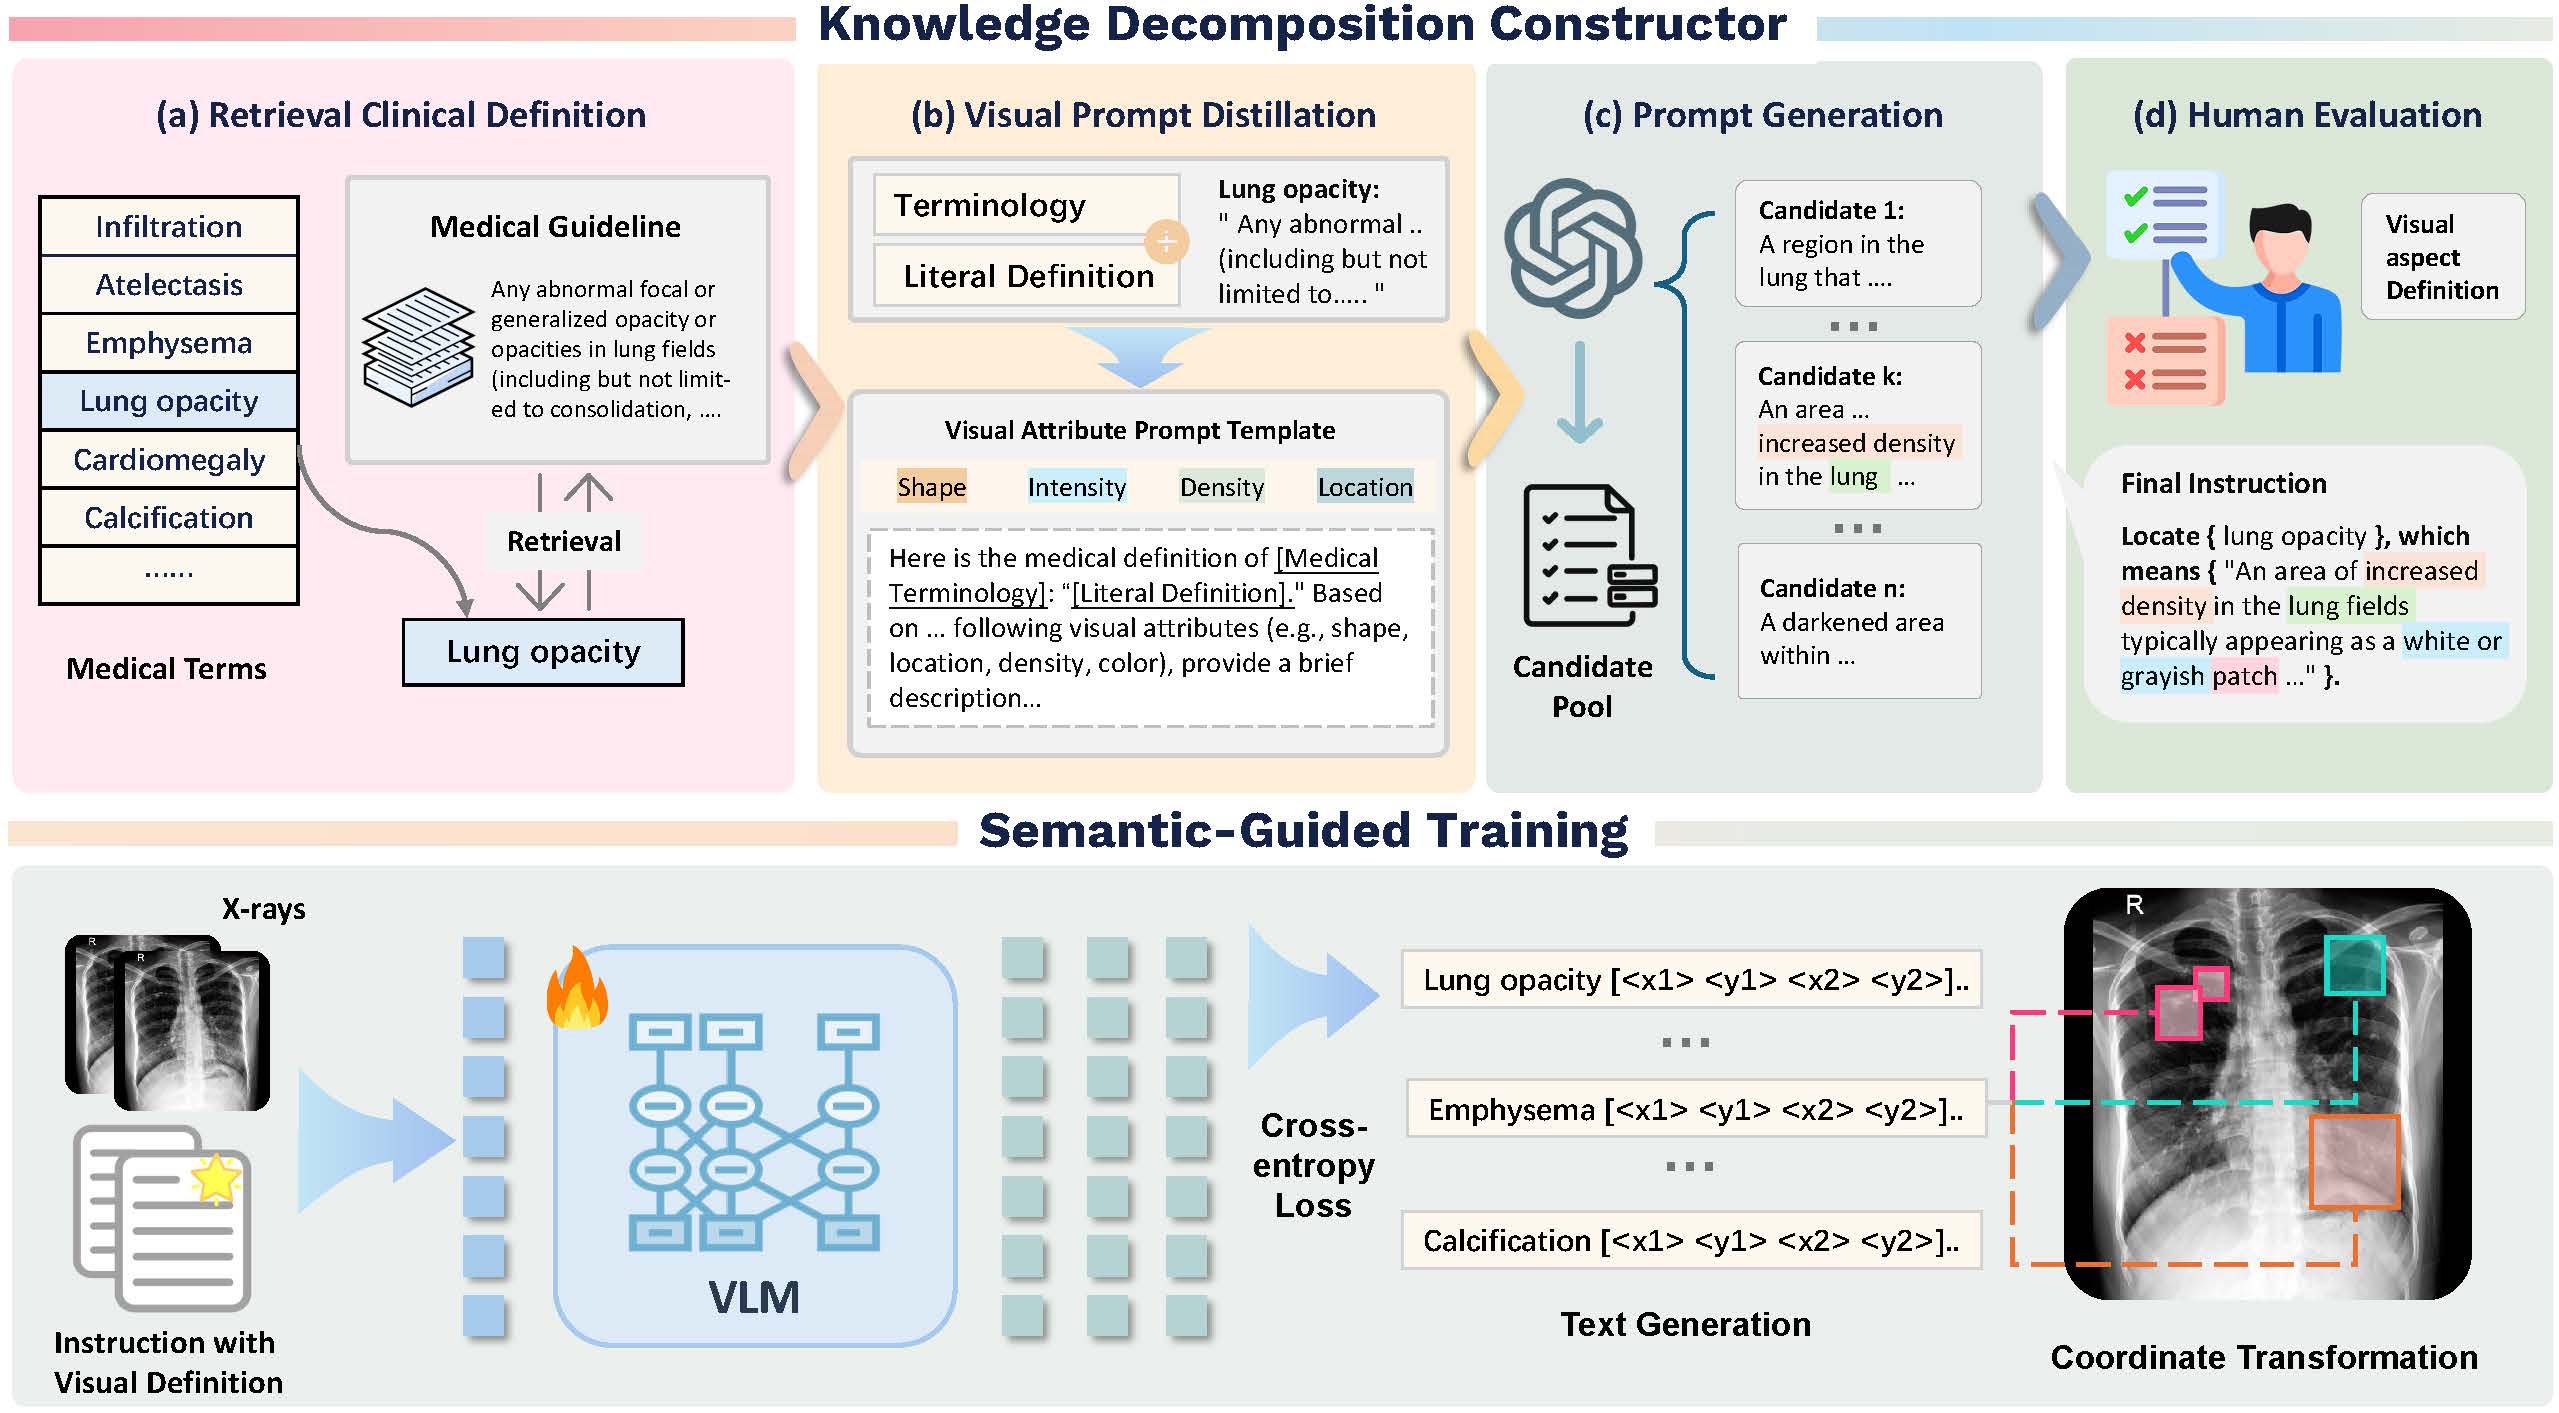

Jun Li, Che Liu, Wenjia Bai, Rossella Arcucci, Cosmin I. Bercea, Julia A. Schnabel.

[paper]

[project]

[huggingface]

Accepted by CVPR 2026 Findings.